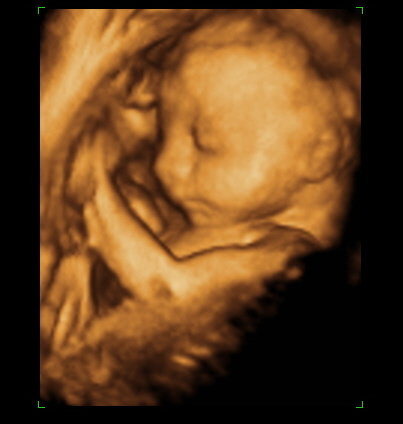

A mi kis álmodozónk